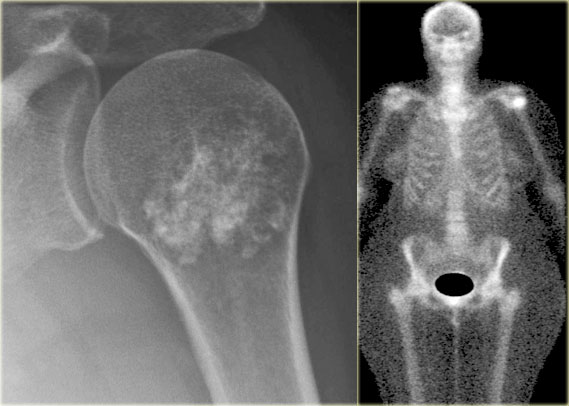

Here a patient with a lesion in the proximal humerus with typical popcorn calcification.

The most likely diagnosis is enchondroma, however progression to a low-grade chondrosarcoma cannot be excluded based on the plain radiograph alone.

There is increased activity on the nuclear bone scan, which is more in favor of the diagnosis of a chondrosarcoma.

This proved to be a low-grade chondrosarcoma.